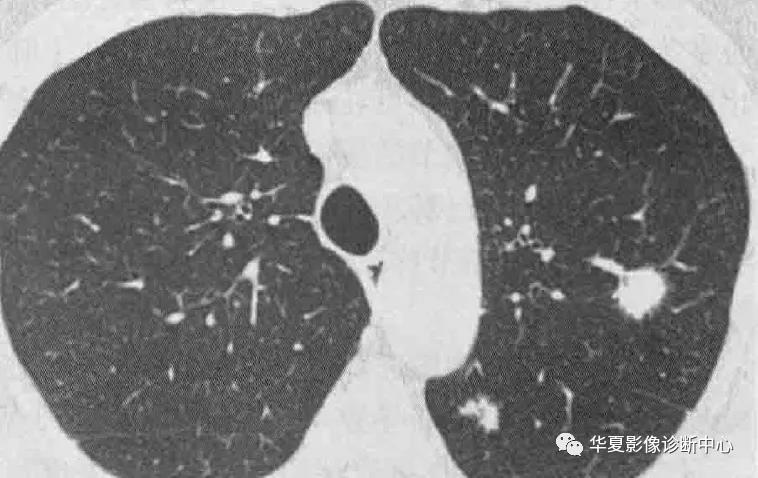

影像学表现:大多数转移性钙化患者X线表现正常,如果异常,表现包括大量直径3-10mm松散的、边界不清的结节灶,类似空腔结节或肺实质病变的斑片状病灶,主要累及上肺,钙化在X线不大明显。CT典型表现为松散的、边界不清的、直径3-10mm结节,位于小叶中心且上叶分布最多,边界可很清楚,结节钙化可是点状、分散的,或偶尔环形,钙化血管典型的可见于胸大肌和胸小肌之间,还可能出现广泛磨玻璃、斑片状实变及肺动脉和左心房壁的钙化。